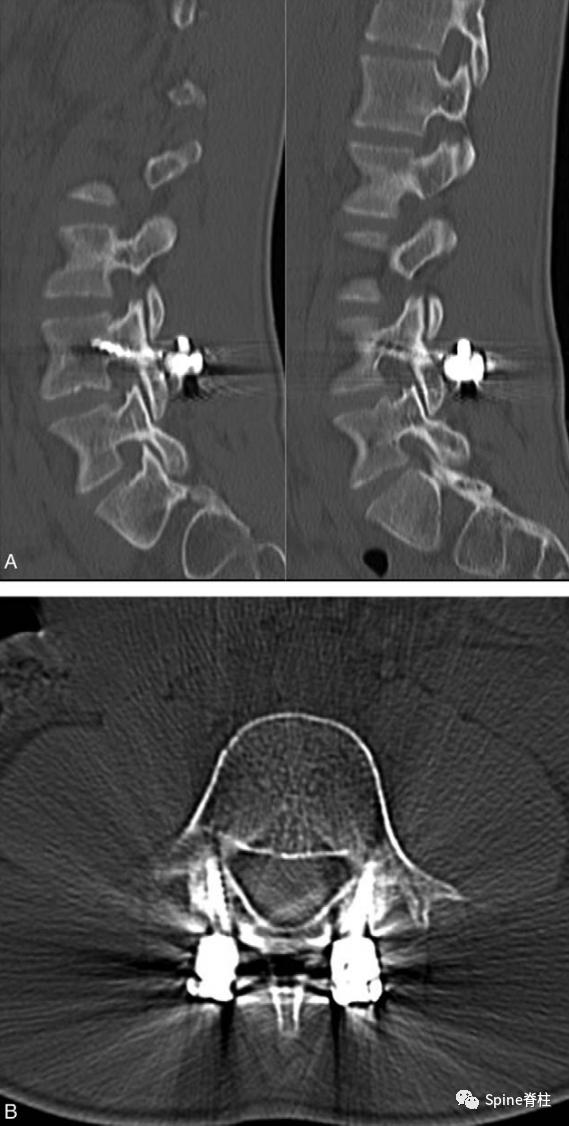

1. 椎弓根螺钉-钉钩系统

PMID: 9199377

PMID: 15699811

PMID: 17520298